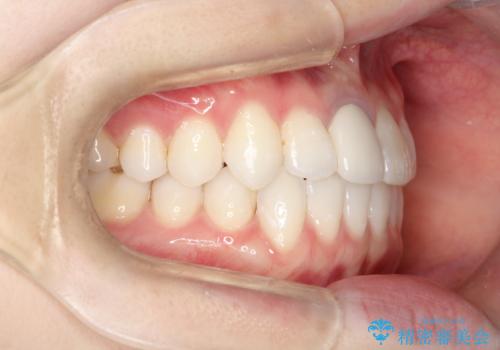

- 前歯の凸凹を主訴に来院されました。

インビザラインにて短期間で満足いく結果が得られたと大変喜ばれました。

歯と歯の間に僅かなスペースを作って配列していました。追加アライナーを1回行っています。